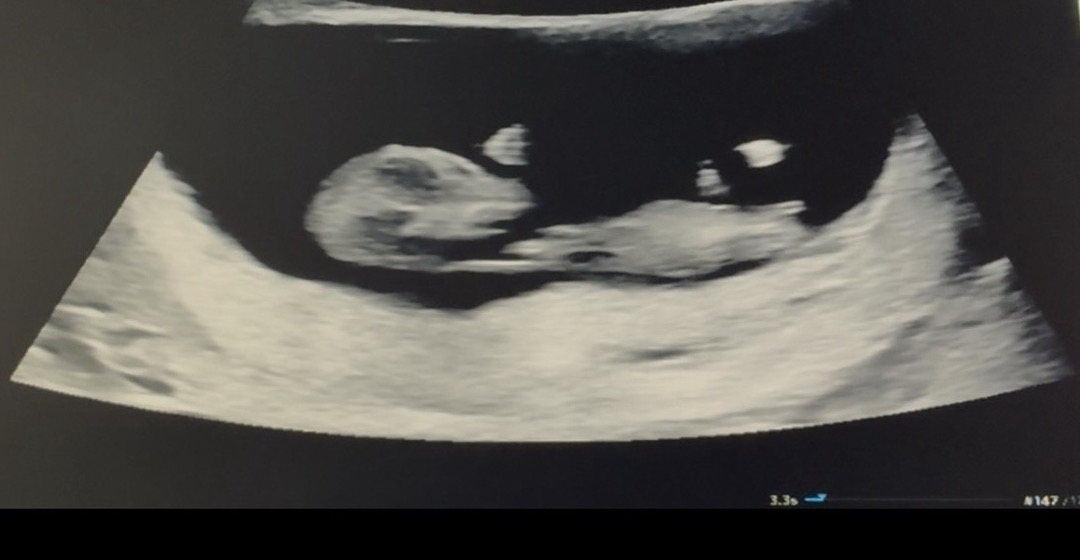

11주5일차.. 각도법 아직 이른가요?

쪼금 이른것 같지만 너무궁금해서ㅠㅋㅋㅋ 빌리AI는 70프로 딸… 아몰랑 많은 참견 부탁드려요 !!